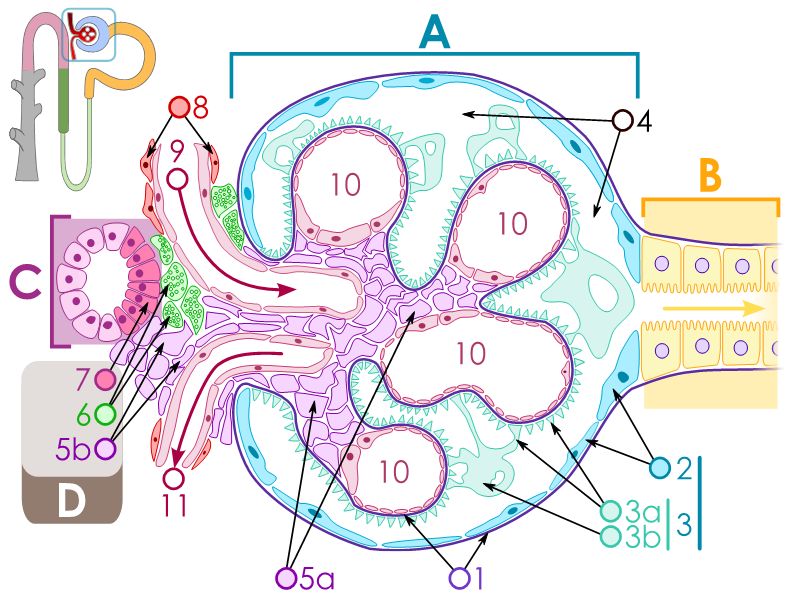

Renal corpuscle

- Tuft of capillaries

- grow into

- Blind end of nephron

- Several layers of epithelium

- Two sides

- Vascular pole

- Tubular pole

Epithelium layers

- Capillary endothelium

- Visceral layer of epithelium

- Podocytes

- Resting on glomerular basement membrane

- Capsular space

- Parietal layer of epithelium

- Simple squamous epithelium

Glomerular filtration barrier

- Three layers

- Fenestrated epithelium

- Exclude blood cells & platelets

- Glomerular basement membrane

- Main filtration barrier

- Thick

- Fused epithelial & endothelial BM

- Replenished by podocytes due to removal by mesangial cells

- Glomerular epithelium

- Through filtration slit

Juxtaglomerular complex

Area where distal convoluted tubule return to glomerulus and pass through the notch between the afferent and efferent arterioles. Modification of the wall of the tubule and afferent arteriole and presence of specialised cells in the connective tissue.Modifications

- Distal convoluted tubule

- Macula densa

- Narrow epithelial cells

- Nuclei densely packed

- CT cells

- Laci cells

- Similar to mesangial cells

- Afferent arteriole

- Modified smooth muscle cells

- Juxtaglomerular cells

- Secretory function

Capillaries

- Supported by

- Mesangial cells

- Mesangial matrix

- Phagocytic

- Maintain basement membrane

- Remove macromolecular deposits

Mesangial cells

- Around capillary loops at vascular pole

- Phagocytic

- Maintain basement membrane

- Remove macromolecular deposits

Podocytes

- Visceral layer of epithelium

- Protrude into capsular space

- Attached to basement membrane

- Long cytoplasmic extensions

- Primary processes

- Secondary processes

- Podocyte feet

- Tightly spaced

- Filtration slits 20 - 30 nm wide